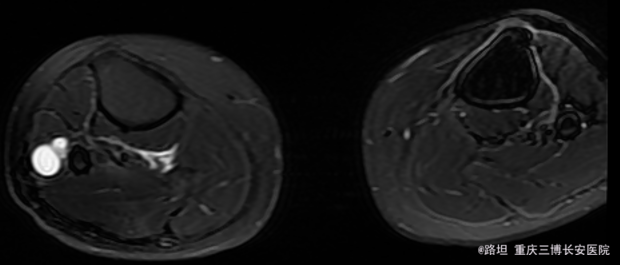

右下肢稍肿胀。皮肤无发红,破损,无窦道。未见明显静脉曲张。右外侧腓骨头扪及大小约40mm*17mm*11mm囊肿,边界清楚,外形较规则,质较硬。

诊断:1.右腓骨头神经鞘膜瘤;2.右侧腓总神经损伤;3.阑尾切除术后; 治疗:硬膜外下行右腓骨头包块切除活检术

神经鞘膜瘤引起腓总神经压迫,足背感觉异常,但是与神经紧密相连,先做活检,再决定是否切除,损伤神经风险高 如何应对术后神经损伤